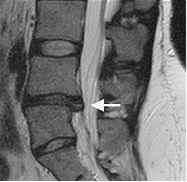

Zervikaler/Lumbaler Bandscheibenvorfall

Im Rahmen degenerativer Verschleißprozesse der Bandscheibe kann es zum Austritt von Bandscheibengewebe in den Wirbelkanal kommen. Durch Bedrängung der dort verlaufenden Nerven kommt es abhängig von der Schädigungshöhe zu Schmerzen, Taubheitsgefühl und Lähmungserscheinungen im Bereich der Arme bzw. Beine. Wird das Rückenmark selbst durch den Druck der Bandscheibe geschädigt, so können Blasen-Mastdarmstörungen oder gar eine Querschnittlähmung auftreten.

Im Normalfall kann der lumbale Bandscheibenvorfall minimalinvasiv mit Hilfe des Mikroskops entfernt werden, ohne dass eine Stabilisierung der Wirbelsäule notwendig ist.